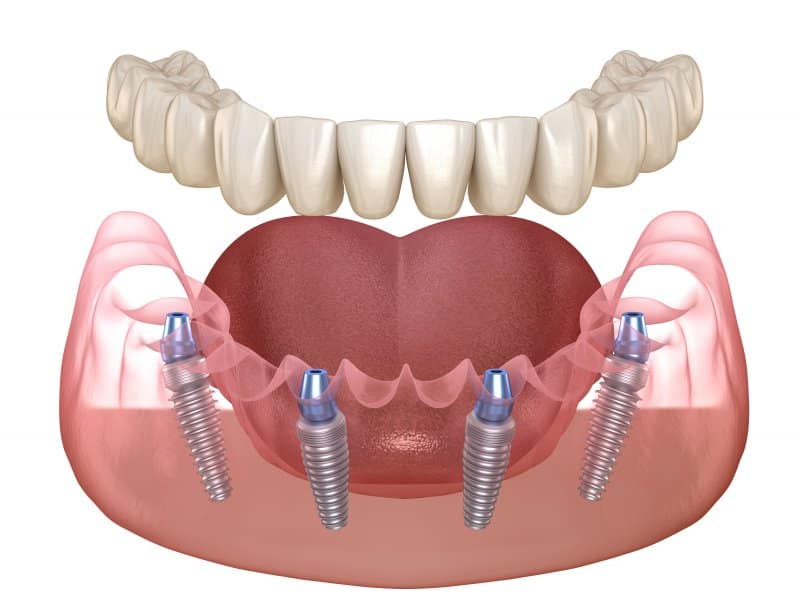

El All-on-4 (Todo sobre Cuatro) es un concepto quirúrgico y protésico desarrollado y patentado por el Dr. Paulo Maló, que se basa en la colocación estratégica de solo cuatro implantes dentales para soportar una prótesis fija completa e inmediata. La genialidad del concepto radica en la posición de esos cuatro implantes:

- Implantes Anteriores: Se colocan dos implantes rectos en la parte frontal de la mandíbula o el maxilar.

- Implantes Posteriores: Se colocan dos implantes en la zona posterior, pero con una inclinación de hasta 45 grados.

Este es el beneficio más apreciado. Si el protocolo se cumple rigurosamente y los cuatro implantes logran la estabilidad primaria, usted recibe una prótesis provisional fija atornillada a sus implantes el día de la cirugía o al día siguiente. No tendrá que pasar tiempo usando una dentadura removible.

La prótesis All-on-4 es fija y no cubre el paladar (en el caso del maxilar superior). Esto mejora drásticamente el gusto, la sensación térmica de los alimentos y la capacidad del habla, devolviendo una función masticatoria estable y segura.

Importante: Aunque la prótesis provisional se coloca de inmediato, la prótesis definitiva se coloca unos meses después (4 a 6 meses), una vez confirmada la osteointegración completa de los implantes.